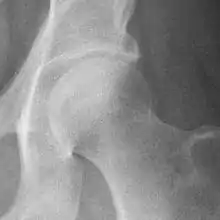

Hip

The most commonly used radiographic classification system for osteoarthritis of the hip joint is the Kellgren–Lawrence system (or KL system).[6] It uses plain radiographs.

| Grade | Description |

|---|---|

| 0 | No radiographic features of osteoarthritis |

| 1 | Possible joint space narrowing (normal joint space is at least 2 mm at the superior acetabulum)[7] and osteophyte formation |

| 2 | Definite osteophyte formation with possible joint space narrowing |

| 3 | Multiple osteophytes, definite joint space narrowing, sclerosis and possible bony deformity |

| 4 | Large osteophytes, marked joint space narrowing, severe sclerosis and definite bony deformity |